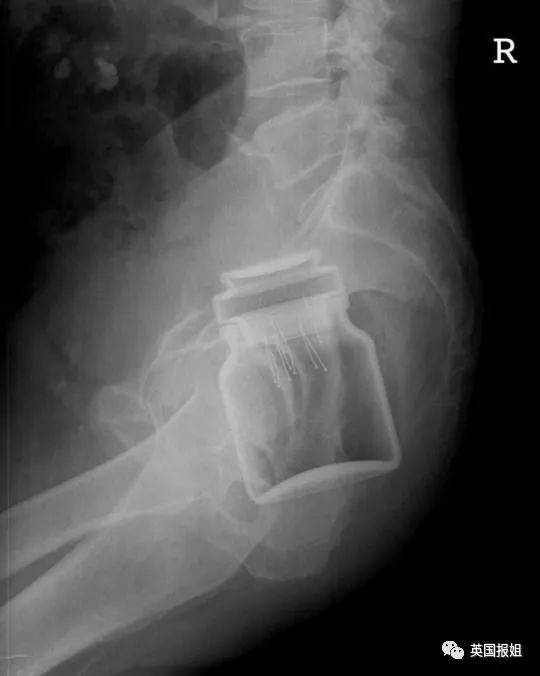

▷速溶咖啡罐 , 盖子上还有别针一名男子把一罐速溶咖啡塞进了自己的直肠 , 而这个咖啡罐盖子内部的橡胶部分还插着很多别针 。他没说为啥要这么做 。从此人类的未解之谜又多了一个 。